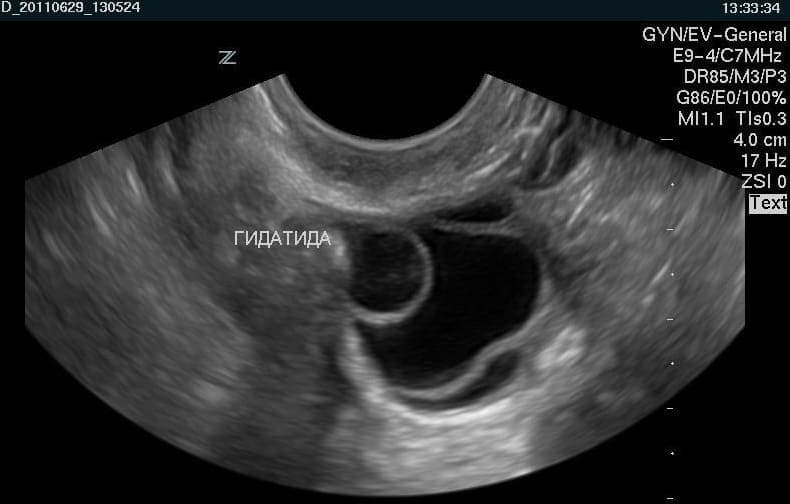

Гидатида Морганьи

Новообразования в виде кист могут возникать как поодиночке, так и группами. Если это одиночные кисты, которые не вызывают беспокойства, их можно не лечить. К тому же они, как правило, не препятствуют беременности. Когда же кист много, то обязательно требуется лечение.

Данные новообразования часто бывают круглой и овальной формы. Поверхность у них гладкая и достигает размера около 2 см.

Кисты висят на ножке, их еще называют привеском фаллопиевых труб. Чтобы проверить женщину на наличие гидатид, требуется ультразвуковое исследование. С его помощью диагностируются маточные трубы на предмет проходимости и новообразований. В случае, когда гидатида вырастает до трех сантиметров в диаметре, она может вызвать неприятные ощущения:

Гидатида яичника – это остаток эмбрионального мюллерова протока. Представляет собой полость размерами 2-8 мм с четкими ровными контурами. Гидатида соединена с яичником тонкой ножкой. Внутри образование содержит прозрачную серозную жидкость.